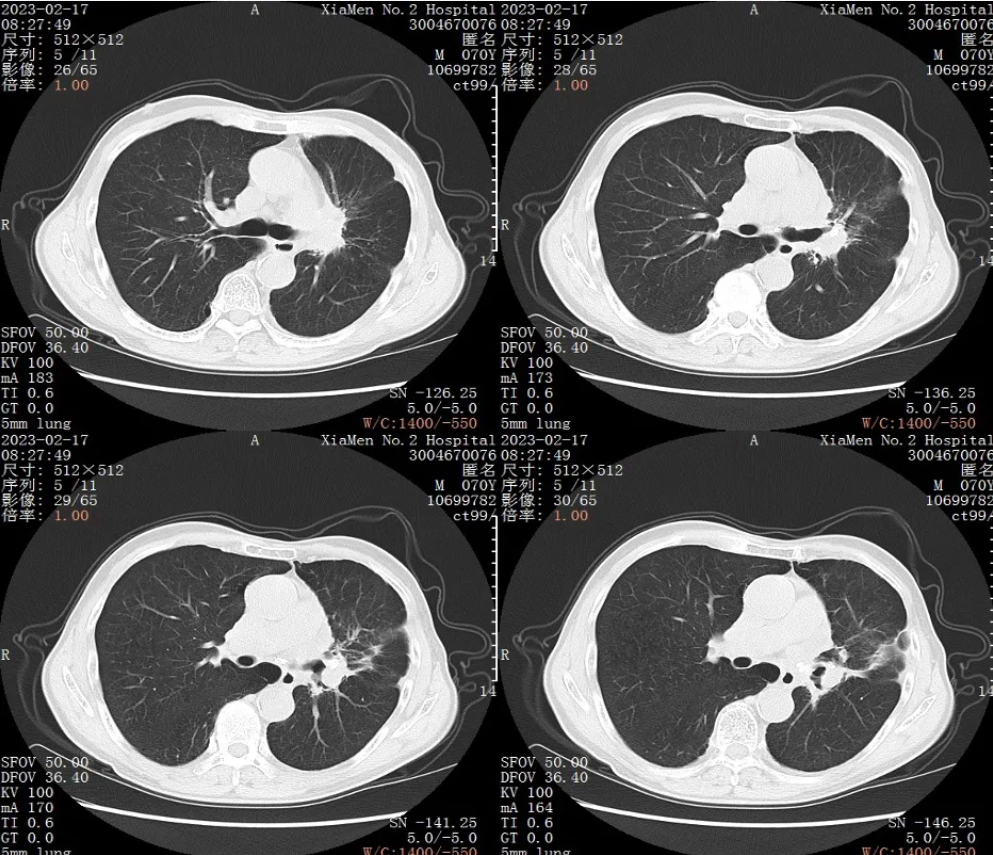

胸部CT平扫+增强:2023年2月17日复查CT

超声支气管镜:左上肺可见新生物

疗效评价:PD(2023年2月17日CT报告提示肿瘤进展)